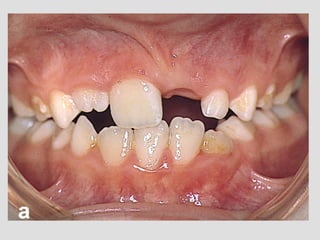

Clinical signs

!

• Mandible deviation to the opposite side

• Chin protrusion

• Open bite on the affected side and cross bite in the

controlateral side

Surgery

Condilectomy of the affected side